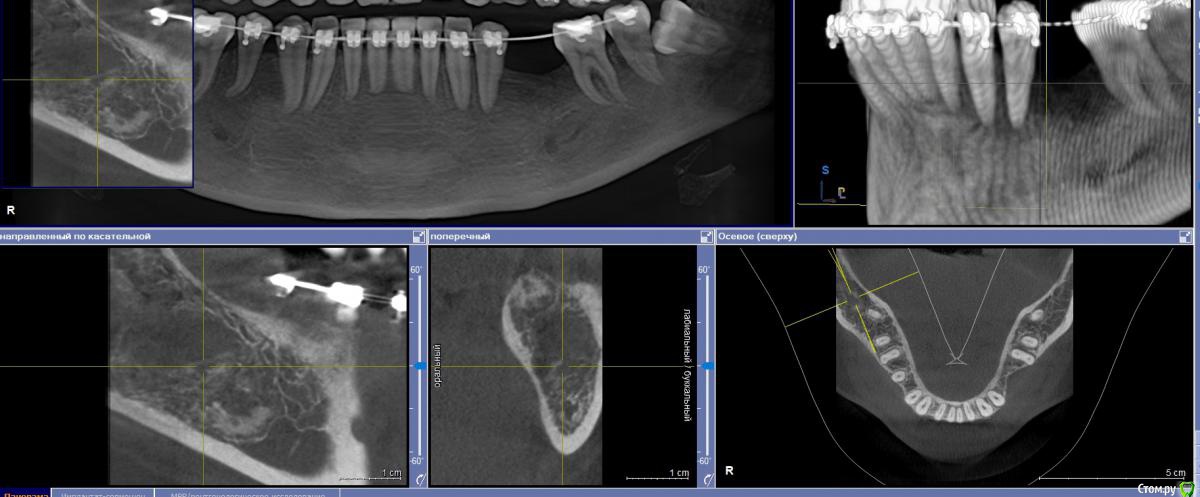

Fin Опубликовано 6 мая, 2020 Поделиться Опубликовано 6 мая, 2020 Здравствуйте коллеги. Пришла пациентка, для установки импланта в обл 3.6. После осмотра КТ обнаружил образование в проекции будущего импланта. В ходе осмотра КТ так же обнаружилось несколько подобных образований по НЧ. Помогите советом, кто сталкивался с подобной ситуацией и что это может быть? Ссылка на комментарий

Дмитрий Л. Опубликовано 6 мая, 2020 Поделиться Опубликовано 6 мая, 2020 Ну сделайте трепан биопсию. Через пару недель можно будет и имплант вкрутить. Я думаю что это костный рисунок. Ссылка на комментарий

wladdX Опубликовано 6 мая, 2020 Поделиться Опубликовано 6 мая, 2020 (изменено) Мне тоже кажется, что вы принимаете балочную структуру и петли н\ч канала за н\образование. Такое встречается иногда. Похожий случай На ОПТГ выглядит уже не так трагично Изменено 6 мая, 2020 пользователем wladdX 1 Ссылка на комментарий

It'sGeorgy Опубликовано 6 мая, 2020 Поделиться Опубликовано 6 мая, 2020 Тоже часто сталкиваюсь с таким. Костный рисунок. 1 Ссылка на комментарий

Fin Опубликовано 7 мая, 2020 Автор Поделиться Опубликовано 7 мая, 2020 Мне тоже кажется, что вы принимаете балочную структуру и петли н\ч канала за н\образование. Такое встречается иногда. Похожий случай46_1.jpg На ОПТГ выглядит уже не так трагичноОПТГ фрагмент.jpgЧестно говоря тоже думаю, что костный рисунок но смутили размеры и то что в других местах кроме этих таких явлений не наблюдается. Сейчас пациент предоставил снимок до ортод. лечения. На нем немного видно костный рисунок. Ссылка на комментарий

Fin Опубликовано 7 мая, 2020 Автор Поделиться Опубликовано 7 мая, 2020 Тоже часто сталкиваюсь с таким. Костный рисунок.Извините, хотел нажать кнопку ответа а поставил минус((.Такое тоже вижу очень часто, но смущают размеры. Ссылка на комментарий